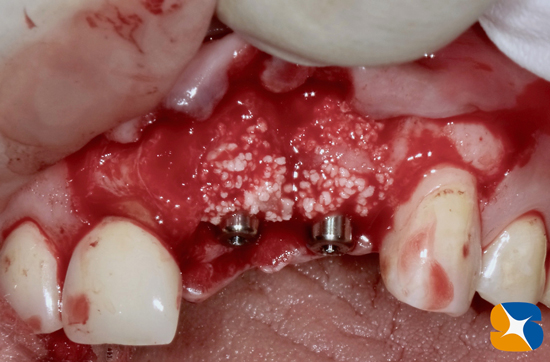

骨から突き抜けたインプラントを撤去

2本のNewインプラント、移植成功。

自己血液を使ってCGFを作り、人口の骨(βーTCP)を骨の欠落部にセッテングしたところです。

使用インプラント:(左)ノーベルバイオケア社製のパラレルCC 直径3.75㎜、長さ13㎜。

(右)アクティブ 直径3.0㎜、長さ13㎜。